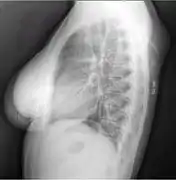

A lipoma is a benign tumor made of fat tissue.[1] They are generally soft to the touch, movable, and painless.[1] They usually occur just under the skin, but occasionally may be deeper.[1] Most are less than 5 cm (2.0 in) in size.[2] Common locations include upper back, shoulders, and abdomen.[4] It is possible to have a number of lipomas.[3]

• Superficial subcutaneous lipomas, the most common type of lipoma, lie just below the surface of the skin.[13] Most occur on the trunk, thigh, and forearm, although they may be found anywhere in the body where fat is located.[14]

Lipomas are usually relatively small with diameters of about 1–3 cm,[42] but in rare cases they can grow over several years into "giant lipomas" that are 10–20 cm across and weigh up to 4–5 kg.[43][44]